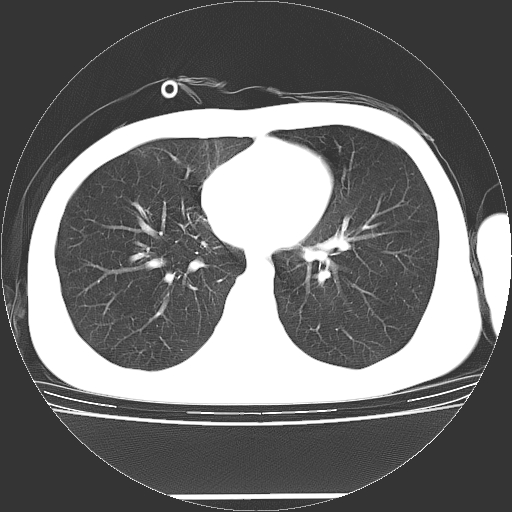

标题: CT19767:男,20岁,右侧气胸行闭式引流术后五天CT检查。 [打印本页]

男,20岁,右侧气胸行闭式引流术后五天ct检查看肺内是否有肺大泡,纵隔窗未见异常,未上传。

1)右侧胸腔闭式引流术后导管留置。2)右肺未见肺大泡。

未见肺大泡,还有微量气体。